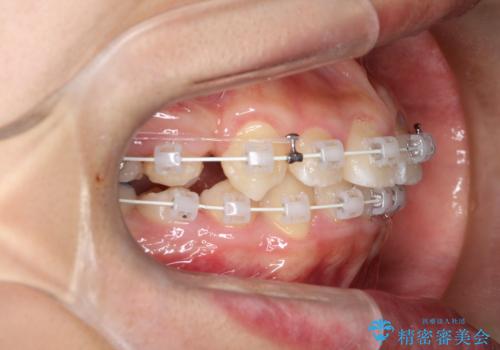

八重歯・歯並びのデコボコとディープバイトを改善した抜歯ワイヤー矯正症例

- 八重歯と咬み合わせを治したいを主訴にご来院された患者様です。

矯正の精密検査の結果上顎左右4番の計2本を抜歯し、審美性に配慮したワイヤー矯正装置(審美装置)を用いて治療を行いました。

八重歯などの歯列のデコボコが綺麗に改善され、患者様にも大変喜んでいただけました。また、咬み合わせが深い「ディープバイト」も併せて改善し、見た目だけでなく機能面でもバランスの取れた咬合を獲得しています。